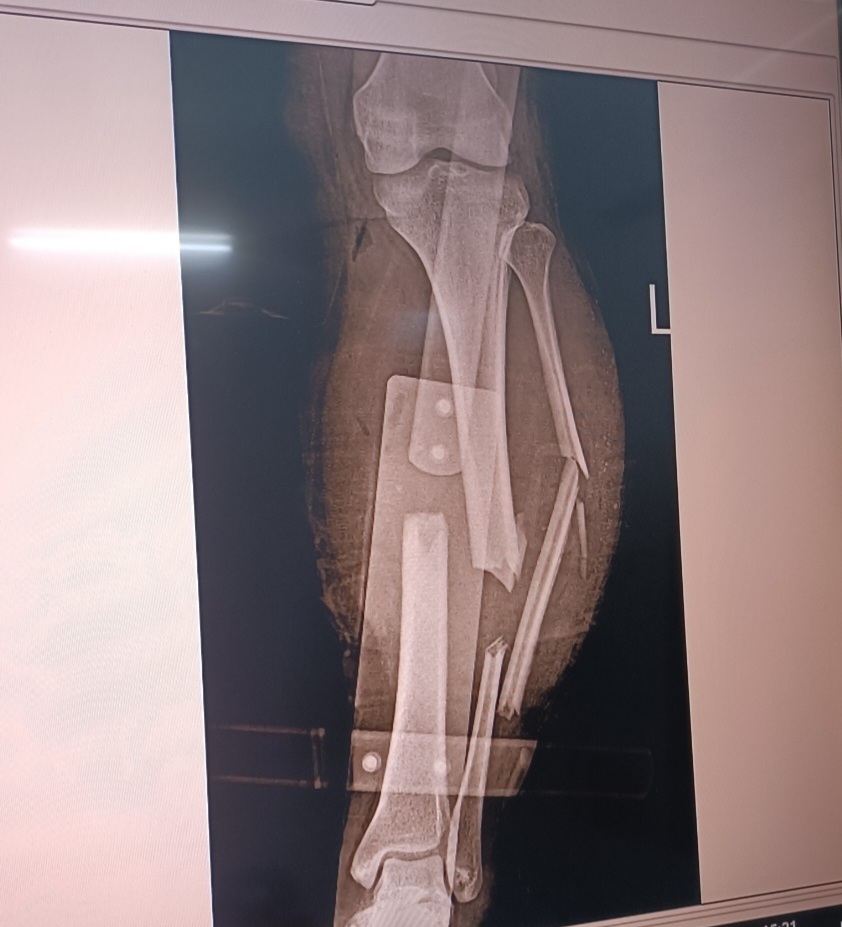

Các bác sỹ đang tiến hành phẫu thuật cho bn N.V.N (Xã Minh Quang)

Ngày 25/10, anh N.V.N (Xã Minh Quang) trong lúc lao động tay của anh bị cuốn vào bánh răng của máy băm gỗ. Sau tai nạn anh được người nhà đưa đến TTYT huyện Chiêm Hoá cấp cứu. Bệnh nhân N có vết thương ở 1/3 trên ngoài cẳng tay phải, nham nhở, kích thước 5x6 cm, mất da che phủ, nhiều vết thương khác nhảm nhở, và có nhiều vết bẩn. Sau khi làm các xét nghiệm cần thiết bệnh nhân được các bác sỹ rửa vết thương và tiến hành phẫu thuật di chuyển vạt da đến che phủ gân cơ vùng mất da. Hiện bệnh nhân đang được điều trị tại khoa Ngoại.